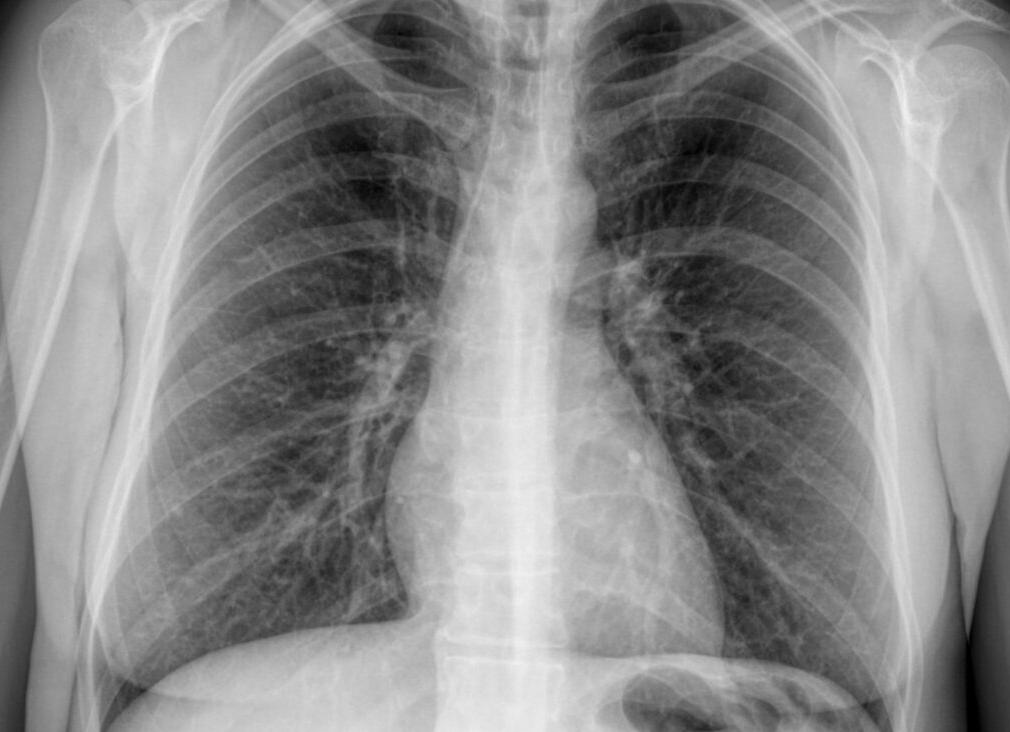

Флюорография легких – исследование органов грудной клетки с помощью рентгеновских лучей, проникающих через легочную ткань и переносящих на пленку посредством флюоресцирующих микроскопических частиц рисунок легких.

Органы грудной клетки по-разному поглощают излучение, поэтому снимок выглядит неоднородным. Сердце, бронхи и бронхиолы выглядят светлыми пятнами, если легкие здоровые, флюорография отобразит легочную ткань однородной и равномерной. А вот если в легких воспаление, на флюорографии, в зависимости от характера изменений воспаленной ткани, будут видны либо затемнения – плотность легочной ткани повышена, либо будут замечены высветленные участки – воздушность ткани достаточно высока.

О чём рассказывает снимок

Процедура является абсолютно безболезненной и достаточно быстро выполняется. Флюорография лёгких показывает наличие заболеваний. Заключение о состоянии органов дыхания может делать только врач-специалист, он внимательно проверяет снимок, но даже плохо знакомый с медициной человек может увидеть, что, если снимок лёгких однороден и нет затемнений, то всё должно быть в норме. Иногда полученный снимок может дополняться следующими формулировками: